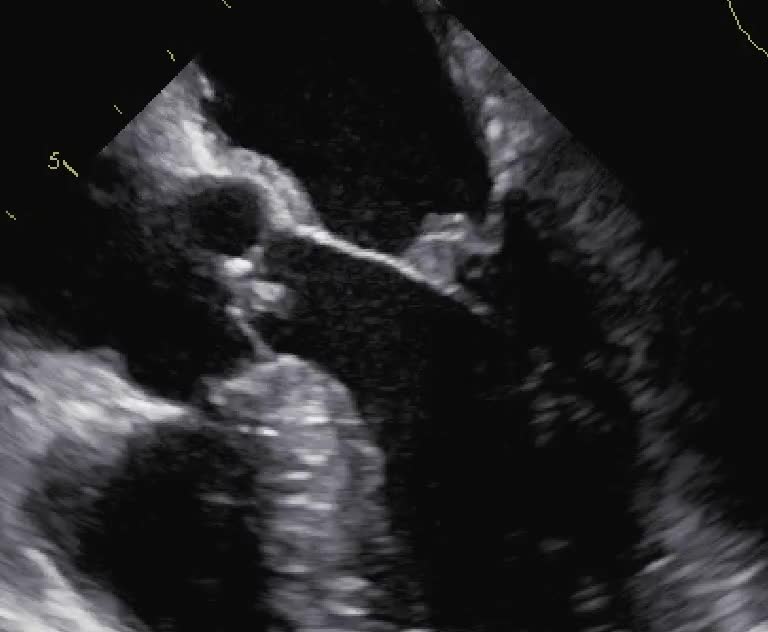

Endocardite su valvola mitrale da candida parapsilosis

Autore:

Manfredo Cerchiello